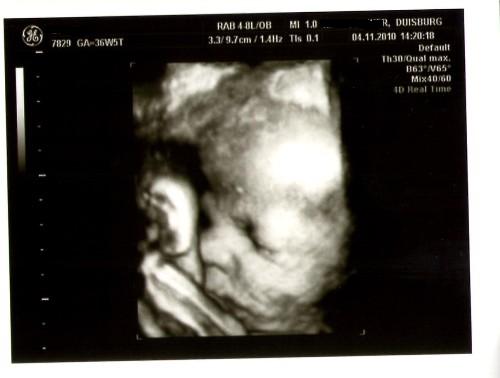

@Liebe Maiar-Steffi: Dein Kleiner voll niedlich ist!!!!!! Ein superklasse Bild vom Köpfchen und Rücken